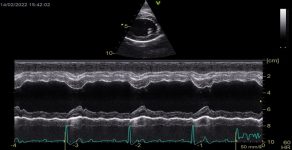

¿Y cómo la evaluamos en la clínica?

Se evalúa principalmente con ecocardiografía:

Flujo transmitral (Doppler pulsado): relación E/A, tiempo de desaceleración.

Haz clic en la imagen para obtener una vista más ampliada

Doppler tisular (TDI): onda e’ (relajación) y E/e’ (estimación de presiones de llenado).

Aurícula izquierda (LA/Ao): refleja cronicidad de la sobrecarga.

Flujo venoso pulmonar (si es posible).

En la disfunción diastólica, el problema está en el llenado ventricular alterado debid

o a rigidez y/o alteraciones estructurales. Y su principal signo clínico es la congestión a nivel pulmonar (si el problema es izquierdo) o abdominal (ascitis) si es del lado derecho.